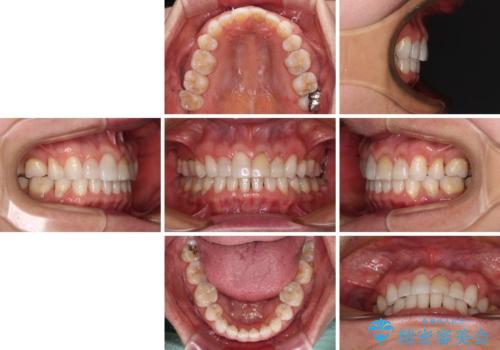

矯正治療の後戻り インビザライン・ライトでの再矯正

- 上下前歯を中心に、以前行った矯正治療の後戻りが気になるとのことで来院された患者様です。

後戻りは軽度であったため、インビザライン・ライトにて治療を行うこととしました。

矯正治療後は、再度後戻りすることを極力回避するために、下顎前歯の舌側を細いワイヤーを用いて保定することとしました。